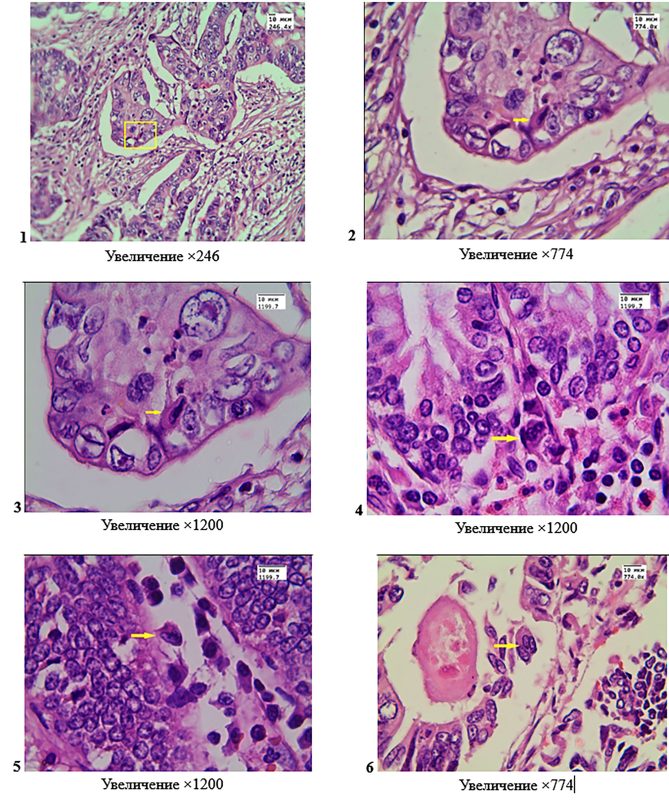

Surgical preparations of resected colon segments for tumors with the structure of moderately differentiated adenocarcinoma, hematoxylin and eosin staining. Photos 1, 2, 3 – a binuclear cell (shown by a square and arrows) with two phenotypically different nuclei, one of which is hyperchromatic; the cell has morphological features of a heterokaryon of hybrid origin; the cell is located among the epithelial cells of the tumor tissue. Photos 4, 5, 6 – among the crypts there are multinuclear cells (shown by arrows), the nuclei of which are phenotypically similar to the nuclei of epithelial cells; the cells are not associated with the basal membrane; photo 6 – a cell in which 3 nuclei are clearly visible due to the fusion of epithelial cells, which indicates its hybrid origin.